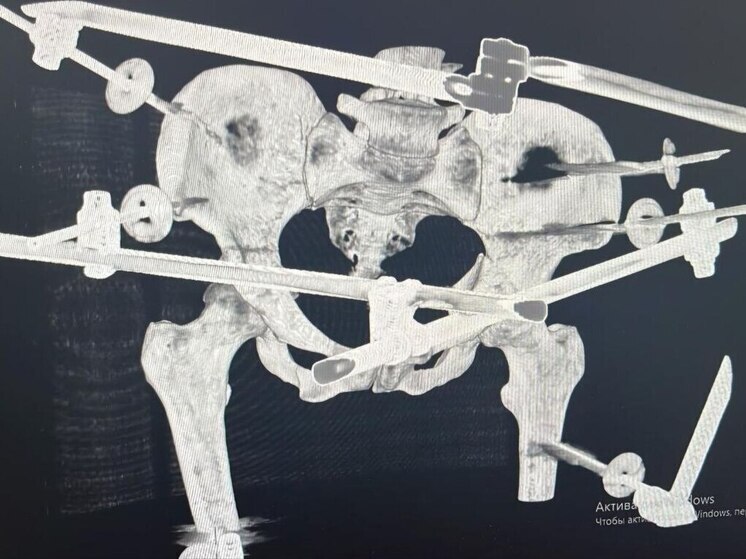

После стабилизации состояния врачи провели сложнейшую операцию: наружную и внутреннюю фиксацию переломов таза и голени, лапароскопию для исключения повреждений внутренних органов, а также первичную обработку ран. Операция прошла без осложнений.